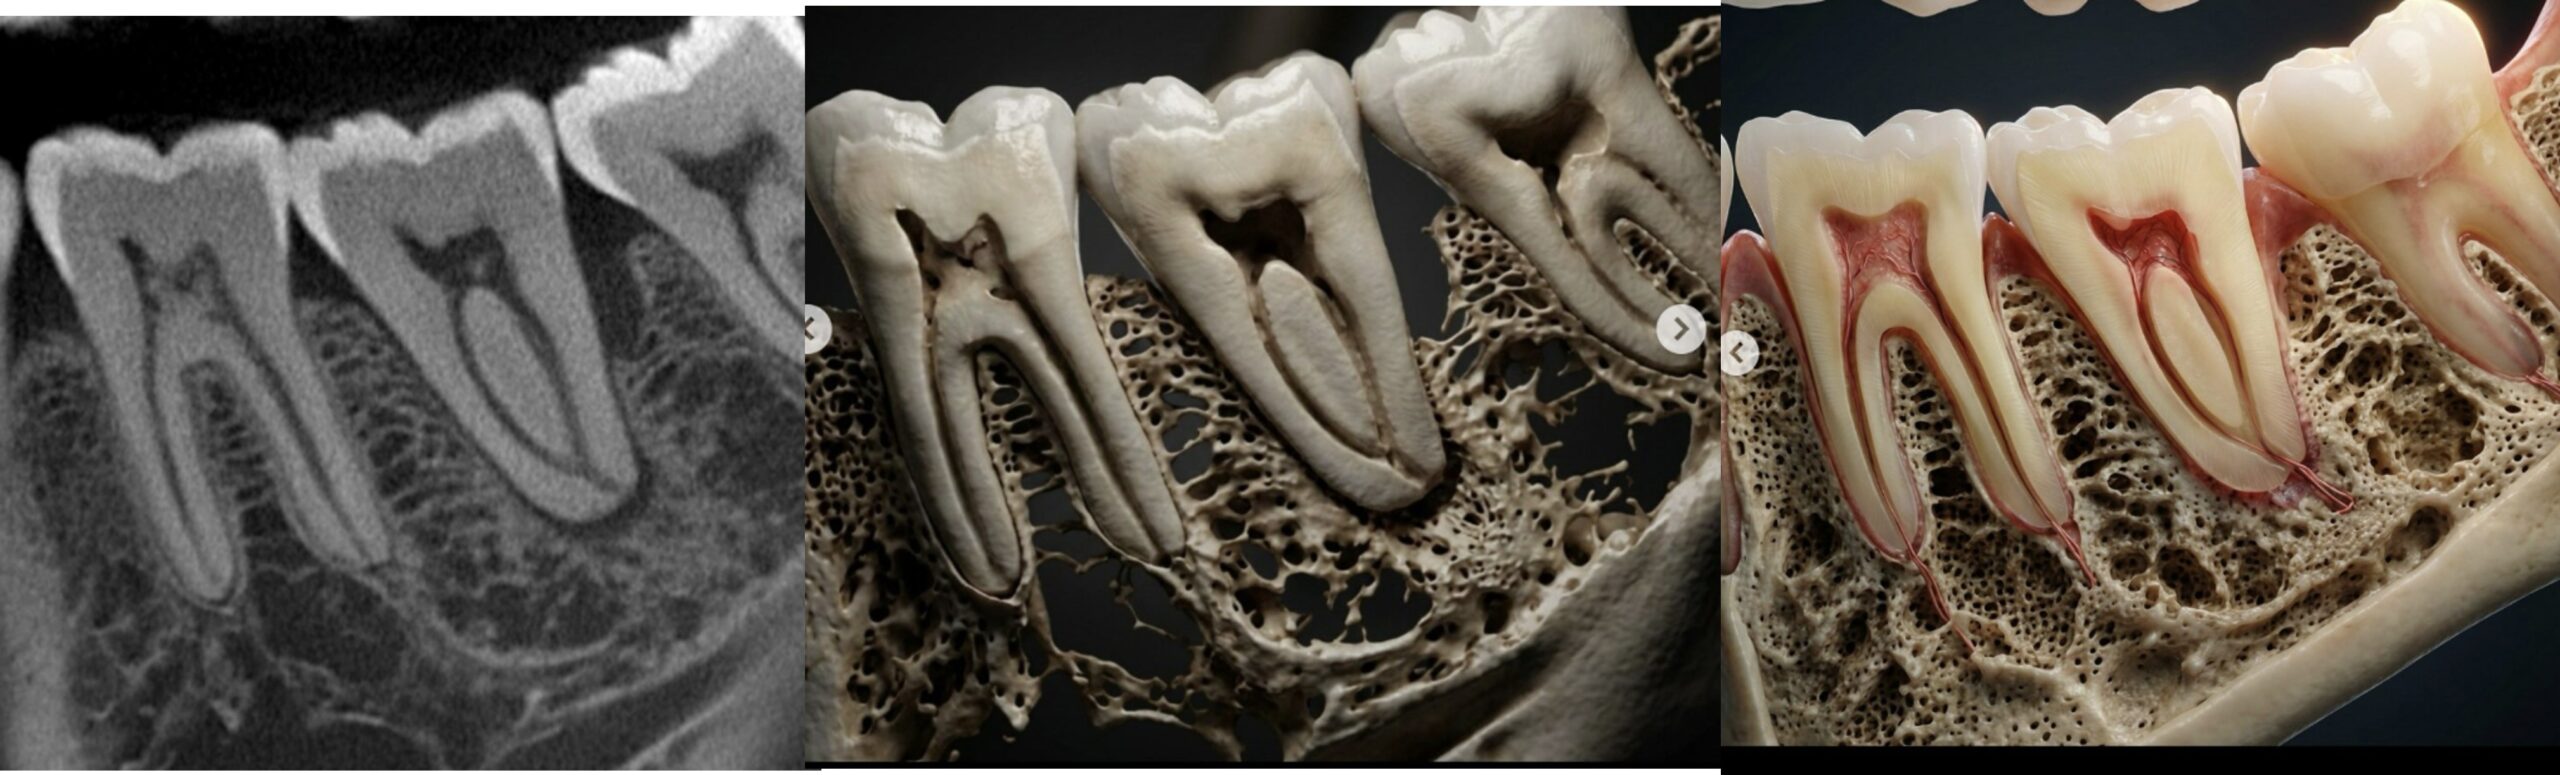

Hands-on training with AI tools to enhance and recolor CBCT data. Create hyper-realistic anatomical renderings using large language model software — images that educate patients and elevate your practice.

One of the most powerful skills you'll gain: using large language model software to transform raw CBCT data into stunning, clinically accurate anatomical renderings. These images revolutionize patient communication and case presentation.